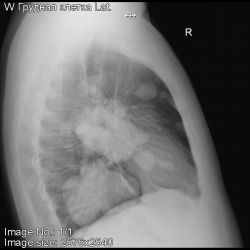

Подскажите, пожайлуста, сделал рентген, обнаруженны множественные образования в обоих легких.

Предпосылки для диагностики были затяжной кашель и температура 37,0-37,5.

На что похожа картина и локация образований?

Рада буду ошибиться. Картина метастатического поражения лёгких. Обращайтесь к онкологу. В первую очередь проверить почки и предстательную железу.

Печально,но поддержу!

Но м.б. Вегенера.

По КТ думаю, что это метастазы. В первую очередь необходимо исключить опухоль яичка (типа семиномы).

Да, на МЕТА семиномы очень похоже

Альтернативным мнение, к сожалению, может быть только по локализации.Это может быть переферическая опухоль левого легкого с МТС в оба легкие.По внешнему виду мтс первоисточник найти крайне затруднительно.Любой первоисточник опухоли может дать разные метастазы.Одни чаще при первичной конкретной опухоли, другие реже.Но мы никогда не знаем процент частоты в данном случае, поэтому определение вида и локализации первичной опухоли только по внешнему виду метастазов проводится только предположительно.Хотя в данном случае это не имеет практического значения для больного.К сожалению.